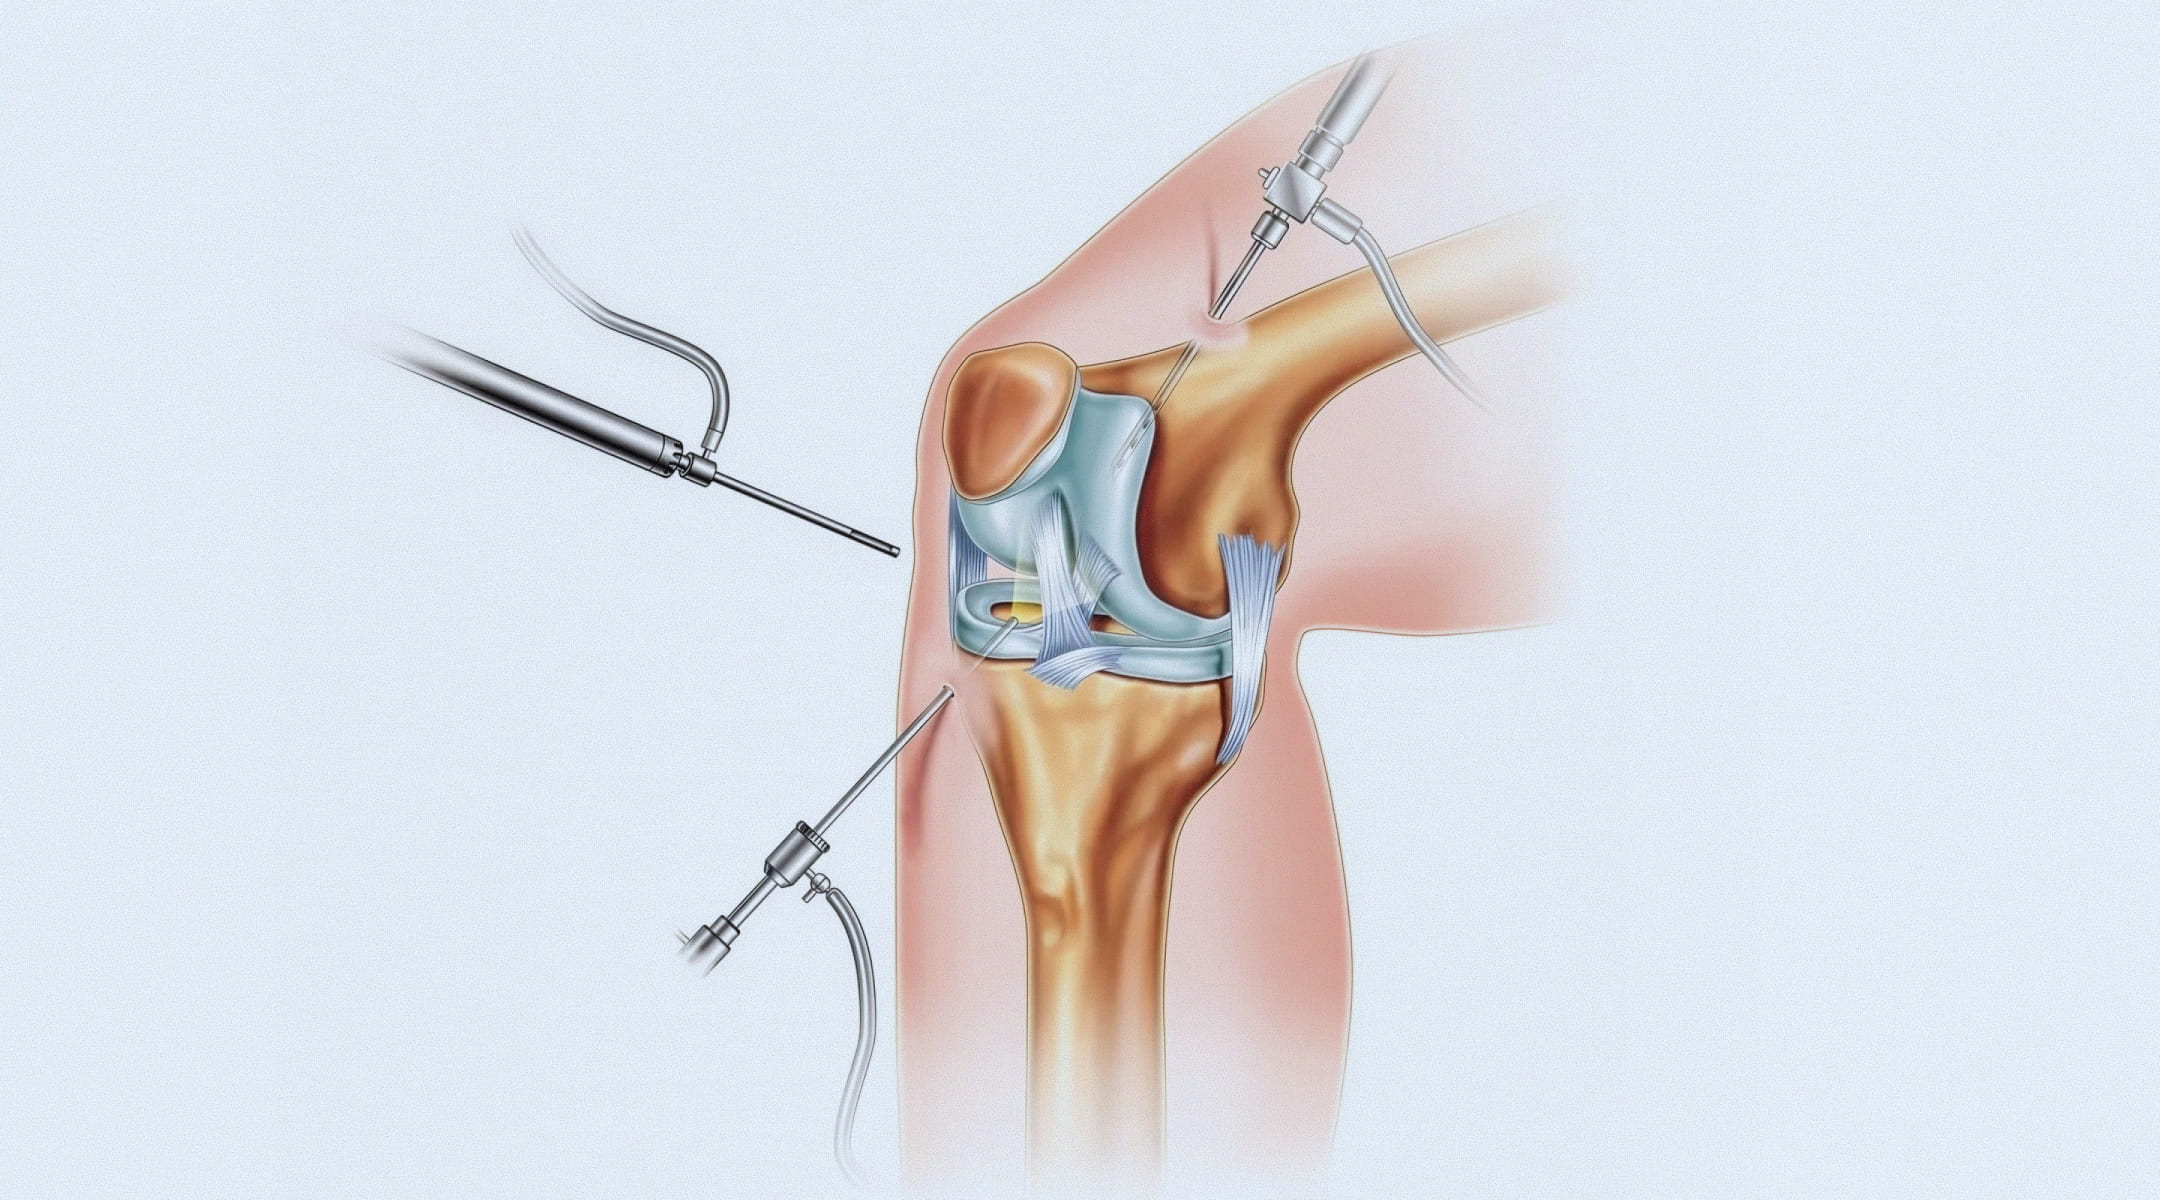

Артроскопия – это высокотехнологичная эндоскопическая процедура, позволяющая хирургу заглянуть внутрь сустава и выполнить необходимые манипуляции через минимальные разрезы (проколы), обычно не превышающие 5-7 мм. В один прокол вводится артроскоп – тонкая трубка с видеокамерой и источником света. Изображение с высоким разрешением передается на экран монитора, многократно увеличивая все структуры сустава. Через второй прокол вводятся миниатюрные инструменты. Такой подход обеспечивает невероятную точность, минимальную травматизацию окружающих тканей, что и делает артроскопическую хирургию столь эффективной.

Операция проводится в стерильных условиях операционной. После обработки кожи и наложения жгута (для минимизации кровопотери) хирург выполняет два-три прокола. Суставная полость заполняется стерильной жидкостью для лучшей визуализации. Врач последовательно осматривает все отделы сустава, оценивая состояние хряща, менисков, связок. После точной диагностики выполняются запланированные вмешательства: резекция или шов мениска при разрыве мениска, операция по стабилизации надколенника, пластика передней крестообразной связки или манипуляции, направленные на восстановление хряща колена. Все действия проводятся под контролем зрения. В конце операции жидкость эвакуируется, в сустав может вводиться лекарственный препарат, на проколы накладываются швы и стерильная повязка. Длительность вмешательства зависит от его сложности – от 30 минут до 1.5 часов.